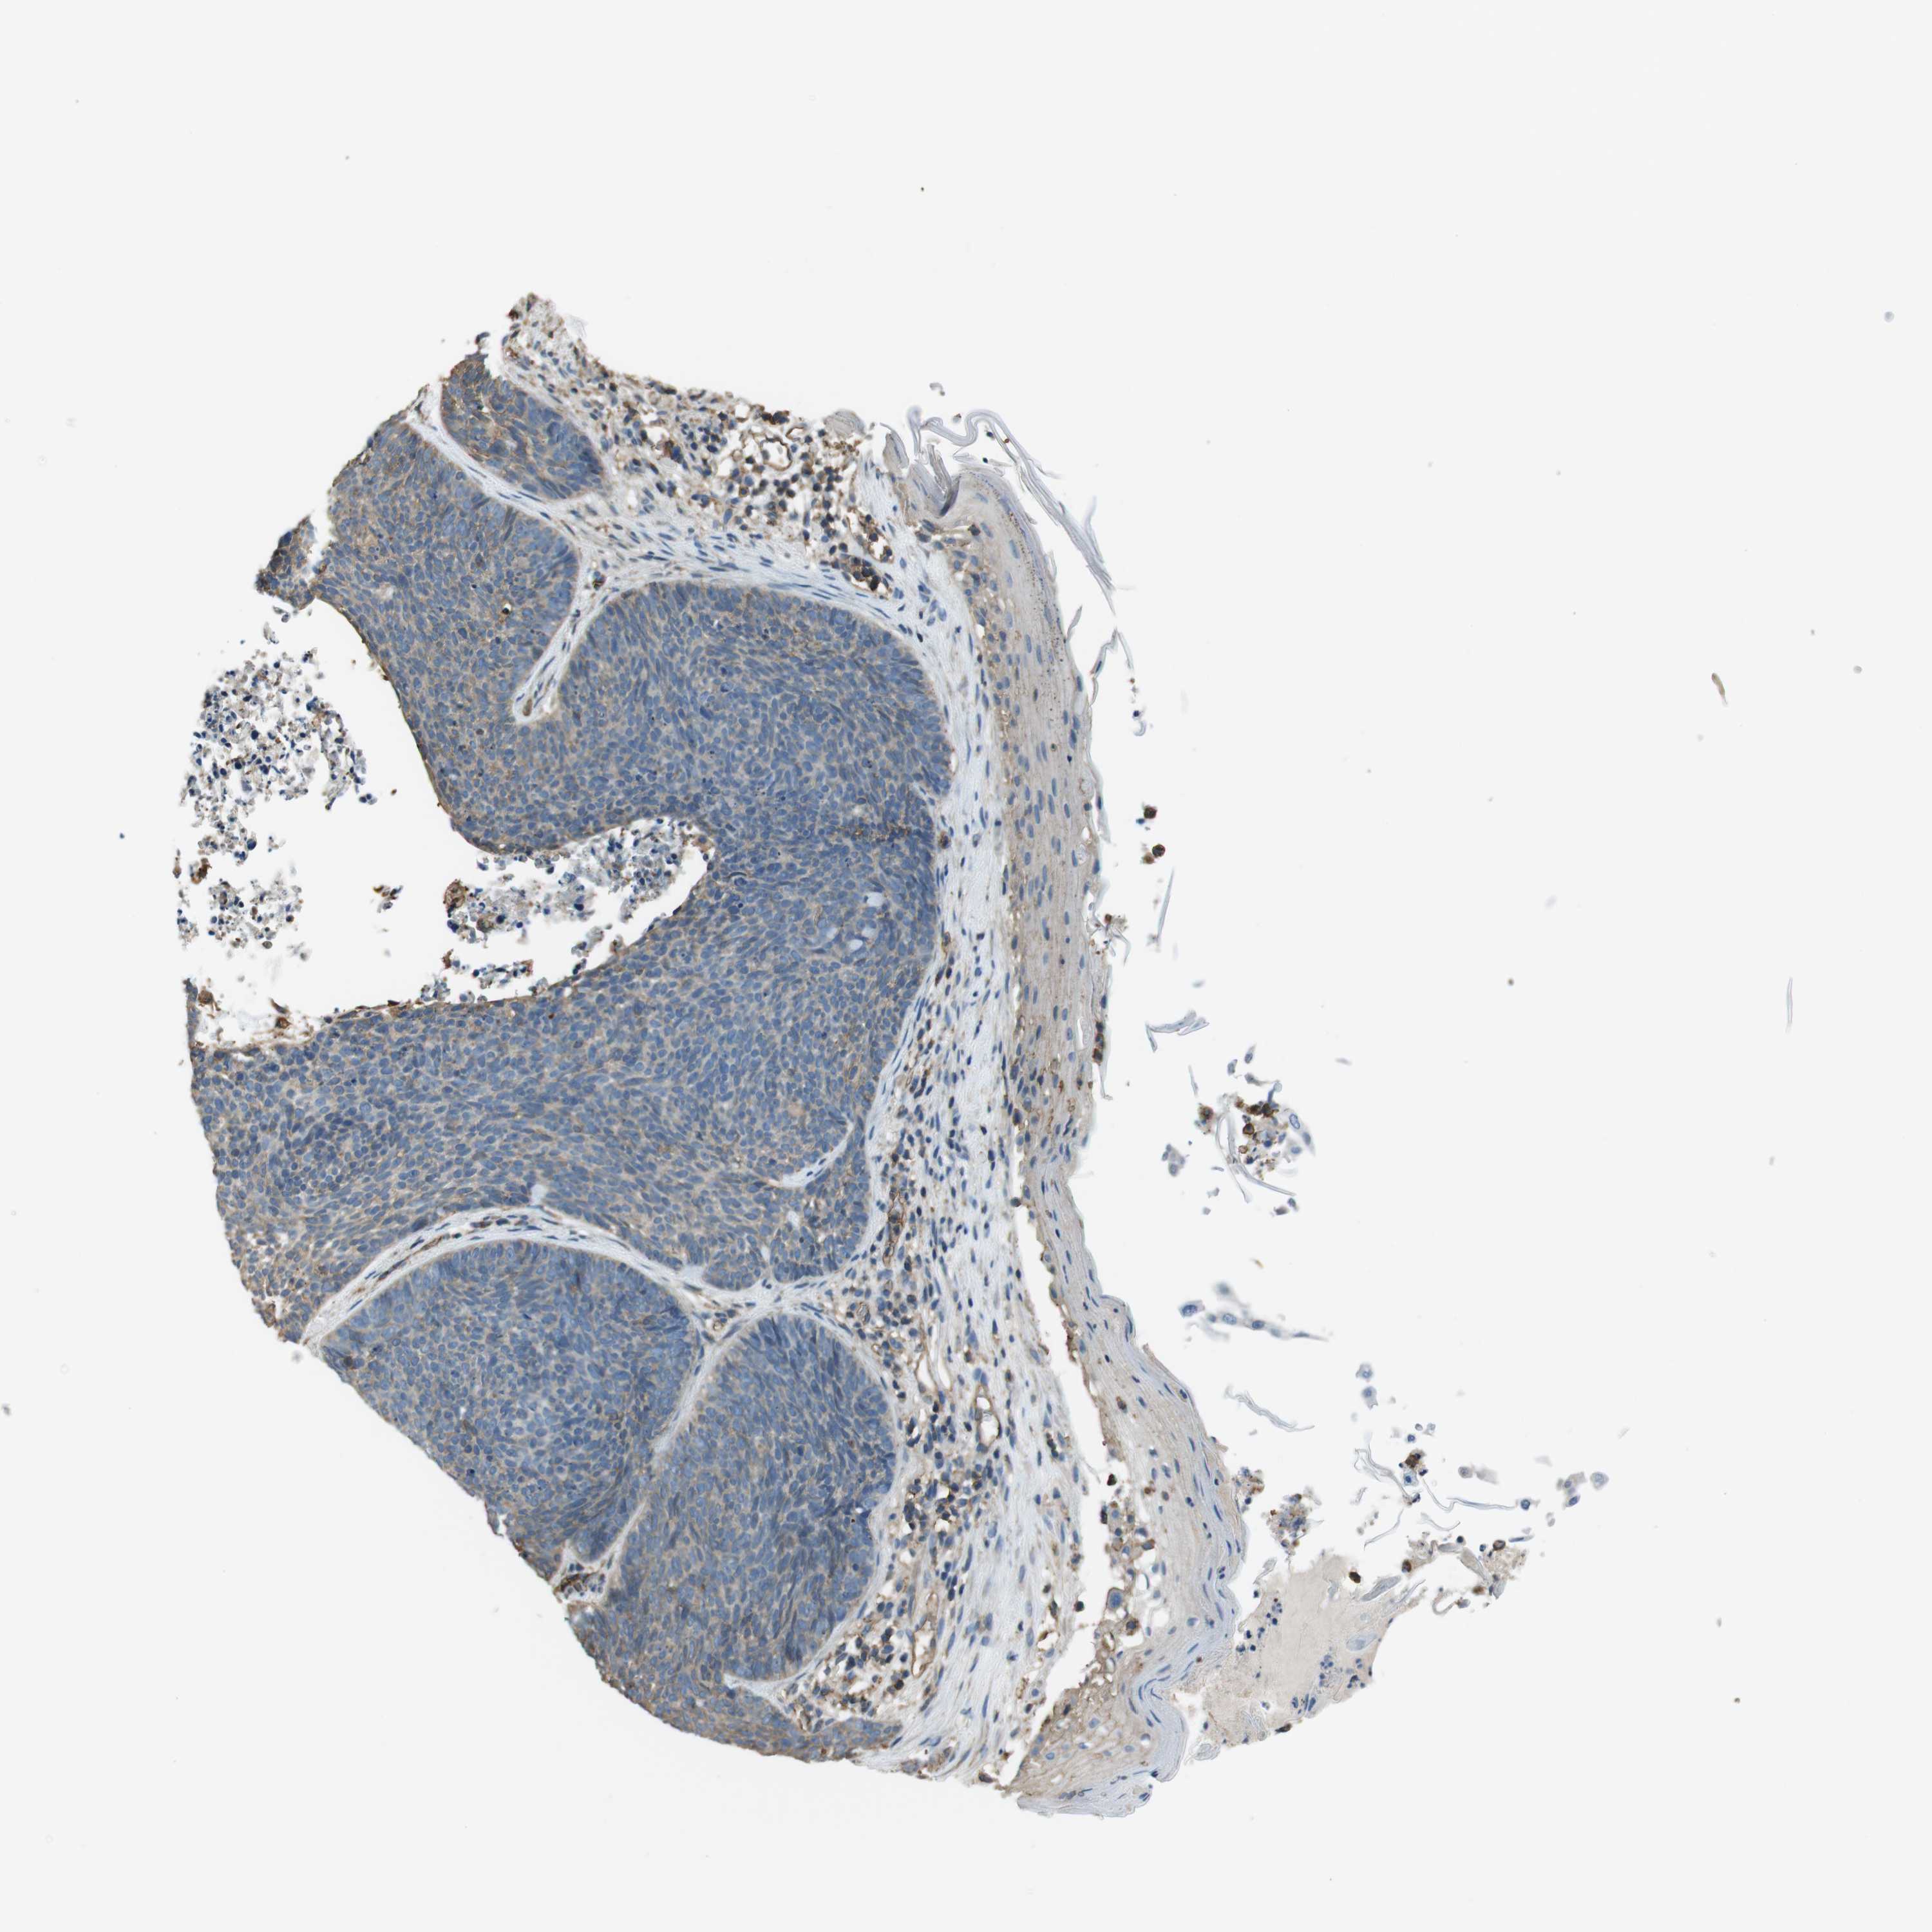

SKIN CANCER - Protein expressioni

A mouse-over function shows sample information and annotation data. Click on an image to view it in a full screen mode. Samples can be filtered based on level of antibody staining by selecting one or several of the following categories: high, medium, low and not detected. The assay and annotation is described here.

Antibody stainingi

Antibody staining in the annotated cell types in the current human tissue is reported as not detected, low, medium, or high, based on conventional immunohistochemistry profiling in selected tissues. This score is based on the combination of the staining intensity and fraction of stained cells.

Each image is clickable and will lead to virtual microscopy that enables deeper exploration of all samples and also displays staining intensity scores, fraction scores and subcellular localization as well as patient and tissue information for each sample.

Antibody HPA014050

Staining

High

Medium

Low

Not detected

Intensity

Strong

Moderate

Weak

Negative

Quantity

>75%

75%-25%

<25%

None

Location

Nuclear

Cytoplasmic/membranous

Cytoplasmic/membranous,nuclear

Squamous cell carcinoma, NOS

Basal cell carcinoma

Adnexal tumor, benign